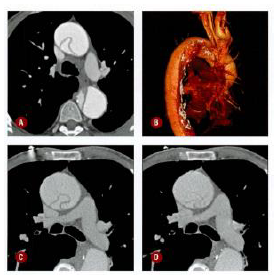

Patologia, Diagnóstico e Tratamento Radioterápico

Homem de 57 anos, hipertenso e usuário de cocaína, procura pronto atendimento por dor torácica há 3 dias, de forte intensidade. Ao analisar a tomografia de tórax com contraste, realizada na admissão, é correto afirmar que

a luz verdadeira tem calibre menor do que a luz falsa.

trata-se de uma dissecção aórtica DeBakey tipo II.